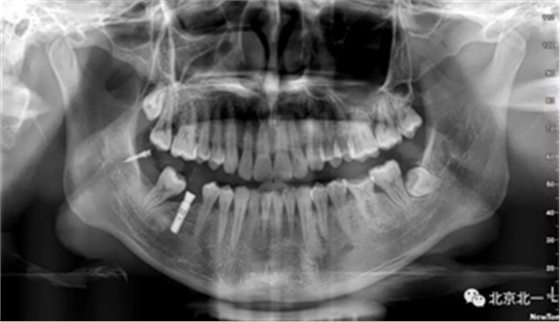

患者、男、40岁,下颌牙缺失数年来院咨询种植。

检查:46缺失, 47倾斜, 1度松动, 未见48萌出,

CBCT:骨量高度及宽度可, 48埋伏,低位阻生.37近中骨吸收

诊断:下颌牙列缺损, 48低位埋伏阻生 37 牙周炎

治疗计划:46种植, 同期拔除48 正畸扶正47.

术后拍片。